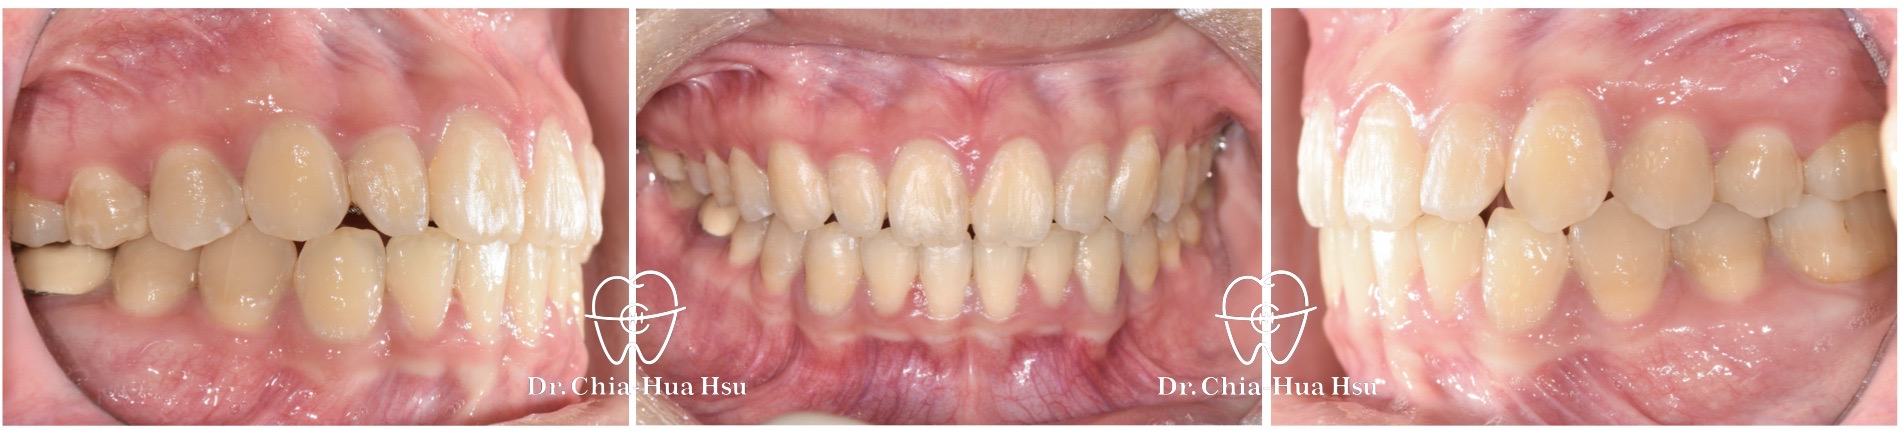

- 治療方式:使用傳統金屬矯正器,搭配二級橡皮筋牽引(Class II elastics)。

- 治療時間:1 年 3 個月。

- 治療結果:齒列排齊,深咬有顯著改善,笑容更有自信。

治療後

治療前